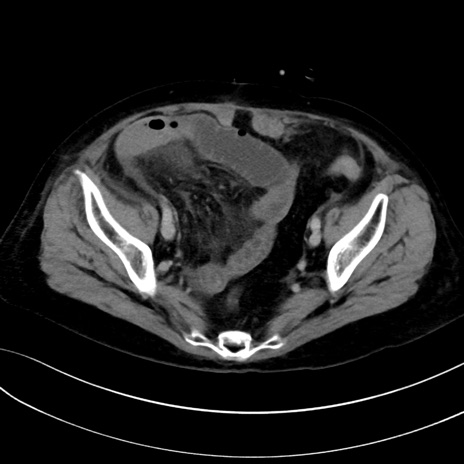

症例13 CT(横断像)1日半後